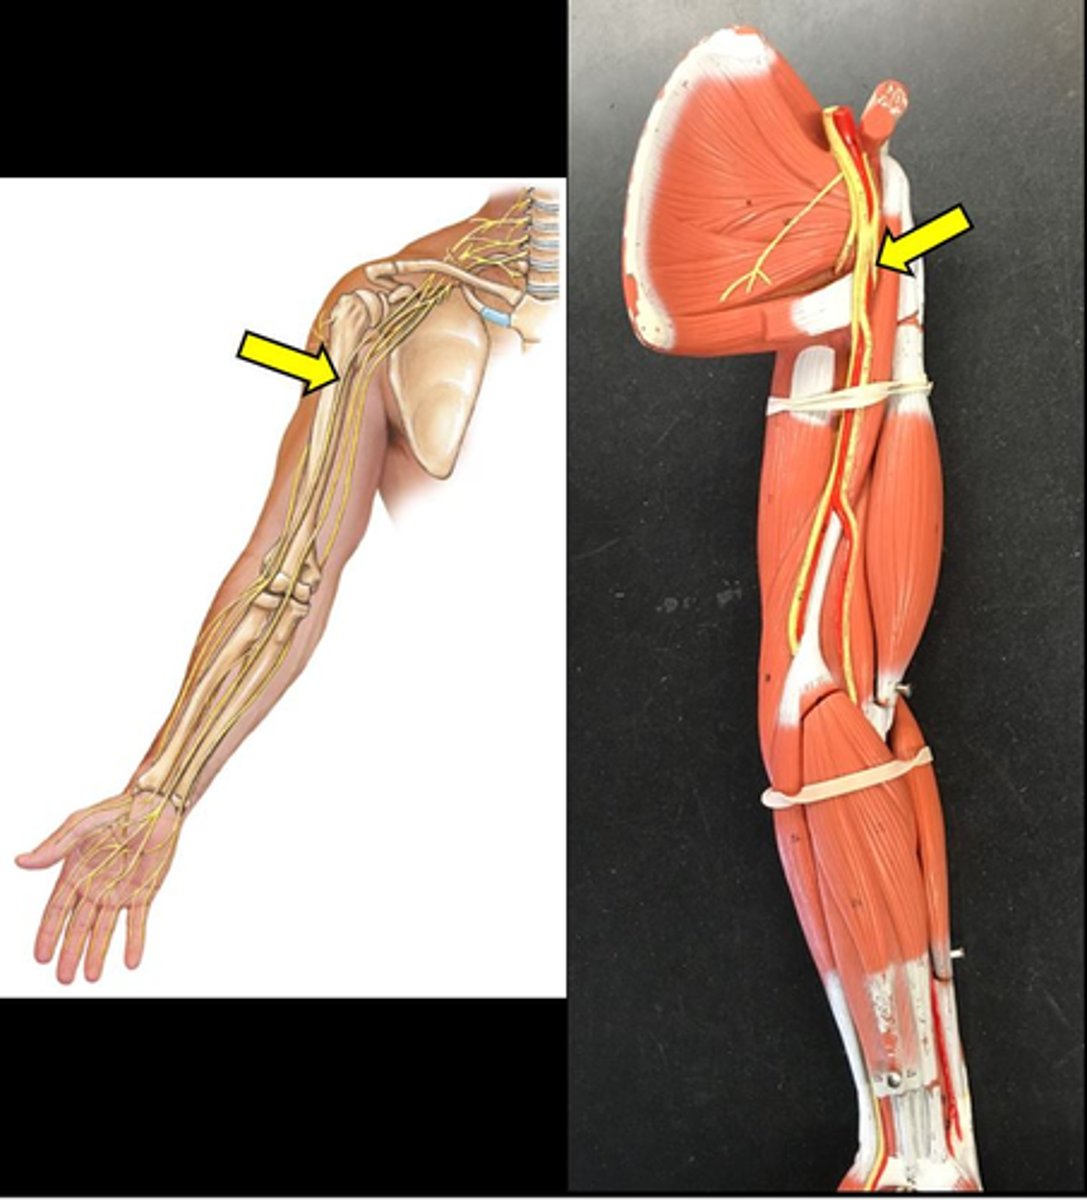

musculocutaneous nerve

median nerve

ulnar nerve

axillary nerve

dives deep near teres major

radial nerve

suprascapular nerve

Branches off the superior trunk

Seen on cadavers or picture

Subscapular nerve